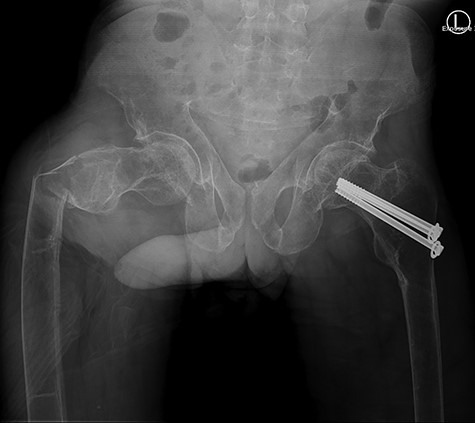

Our patient was discharged from the hospital 14 days after the surgery. The long hospital stay was mostly due to the management of the renal Fanconi syndrome. He was able to mobilize with crutches at time of discharge. The in-hospital stay was without complications. Eight weeks postoperatively our patient returned to our outpatient clinic. Full mobilization was possible and there was a full range of motion. Conventional imaging showed an adequate position of our hybrid osteosynthesis (Fig. 3) and an almost completely healed fracture site.

Post-operative anterior–posterior view: DHS osteosynthesis with intramedullary bone enhancement.